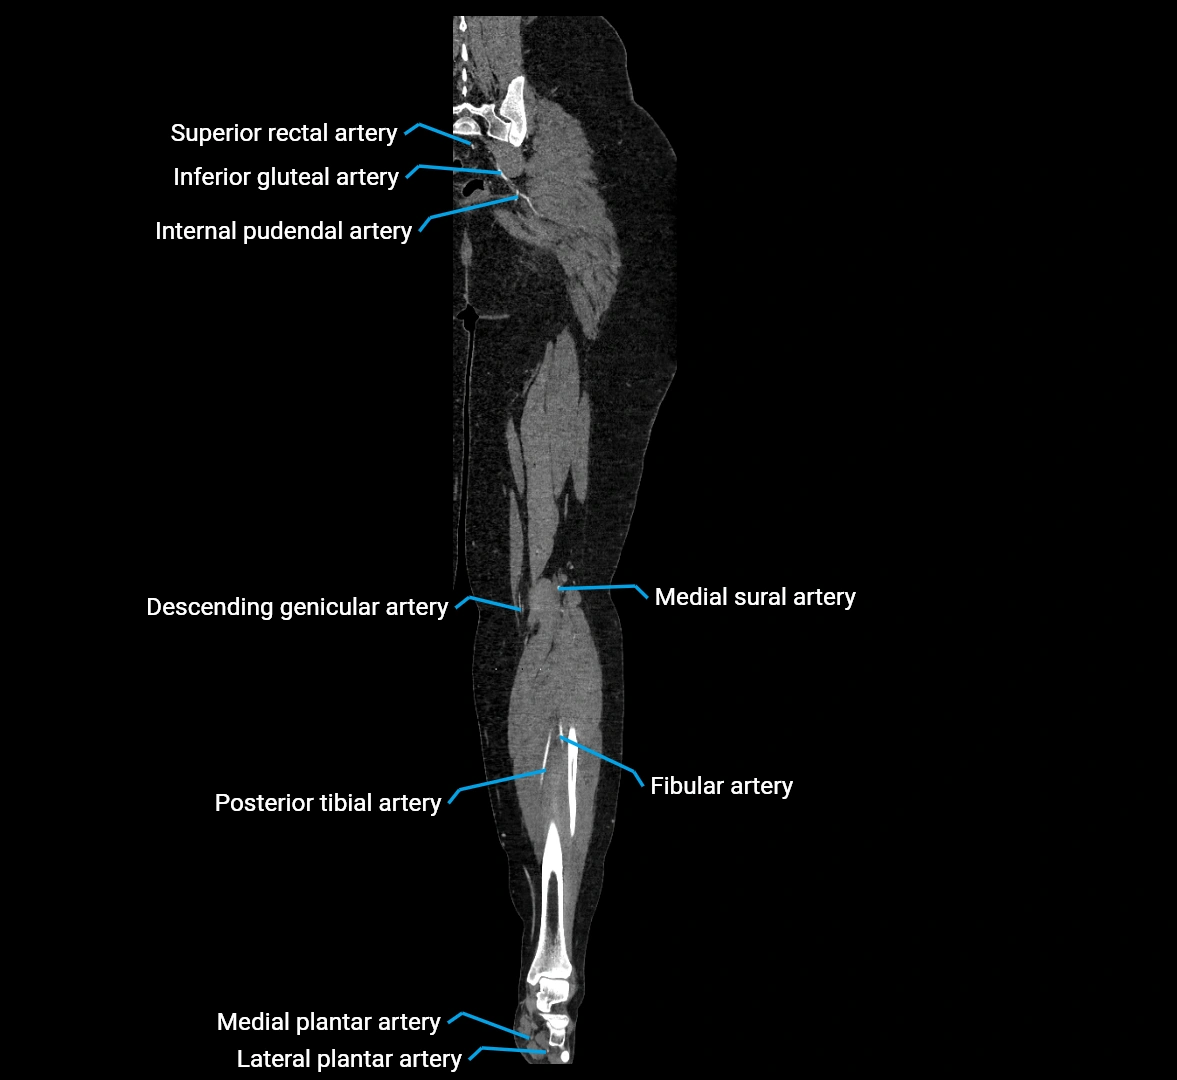

Contrast-enhanced CT (CTA):

• Gold standard for abdominal aortic imaging

• Provides excellent detail of lumen, wall, aneurysm, thrombus, and branch vessels

• Multiplanar and 3D reconstructions help in aneurysm measurement, stent graft planning, and dissection evaluation

• Detects acute rupture, traumatic injury, or occlusion with high sensitivity